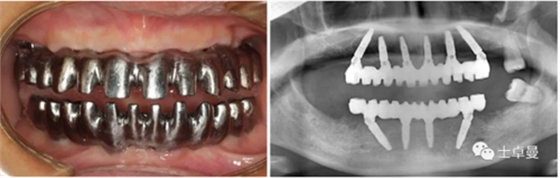

a11.png

a12.png

手術(shù)完成后復查CBCT與術(shù)前設(shè)計對比,驗證植入精度。

a13.png

鈦支架口內(nèi)試戴及X線檢查;

a26.png